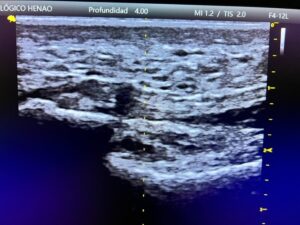

En Centro Podológico Henao utilizamos la ecografía musculoesquelética como herramienta fundamental, no solo para confirmar un diagnóstico, sino para ver exactamente qué le está pasando al tejido en tiempo real.

Durante la exploración clínica, ya identificamos dolor localizado en la inserción medial de la fascia plantar, acompañado de una marcada rigidez y pérdida de elasticidad. Pero fue la ecografía la que nos reveló el cuadro completo.

Lo que encontramos en la ecografía:

- Engrosamiento significativo de la fascia plantar (por encima de los valores normales)

- Alteración de la ecoestructura: la textura interna del tejido ya no era homogénea

- Cambios degenerativos compatibles con fasciopatía crónica

- Ausencia de signos de rotura aguda: buena noticia, el tejido no estaba roto

- Sin hallazgos de inflamación activa: confirmación de que esto ya NO era una fascitis

Este último punto fue determinante. Confirmó lo que sospechábamos: María no necesitaba más antiinflamatorios ni más reposo. Necesitaba un enfoque completamente diferente, orientado a regenerar un tejido que había perdido su capacidad normal de adaptación.

La ecografía no solo nos sirvió para el diagnóstico. También la utilizamos durante el tratamiento como guía para actuar con precisión directamente sobre la zona alterada. Esto es lo que llamamos un abordaje ecoguiado.